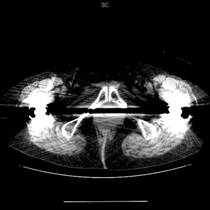

逐次近似法を用いたノイズ低減処理(GE製の場合はASiR:Adaptive Statistical Iterative Reconstructionという名称)とは、システム統計モデルに加えて、解剖学的構造も考慮した、新しい画像再構成法です。この手法は、空間分解能に影響を与えることなく、画像ノイズを削減する画像再構成アルゴリズムで、画質の向上、被ばくの低減を実現できます。

スペクトラルCTイメージングを行う際には2つの異なるエネルギー、低エネルギーと高エネルギーでの撮影データが必要となります。また、データを収集する際には2つのデータ間にエネルギー以外の差異、すなわち位置ずれやタイミングのずれがないことが大前提となります。さらには、ビームハードニングアーチファクトの補正が間違いなく出来ていることも非常に重要な要素となります。